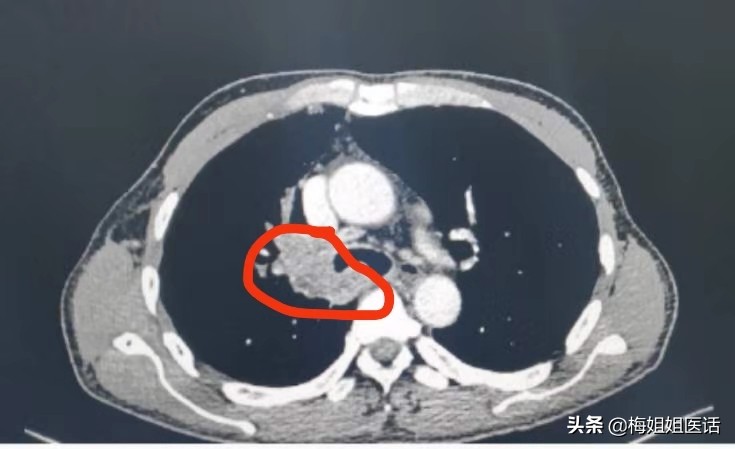

现实中,话说近日病房出院的肺癌患者,正好65岁,患者因“右胸背痛、咯血”入院,经过一系列检查,诊断右肺中央型鳞癌。

肺癌治疗前

化疗3个周期。胸痛咯血症状消失,状态一天比一天好。才复查评估前期治疗疗效。可以看到治疗后病变明显好转(红圈里的肿瘤几乎消失了)。病情缓解。